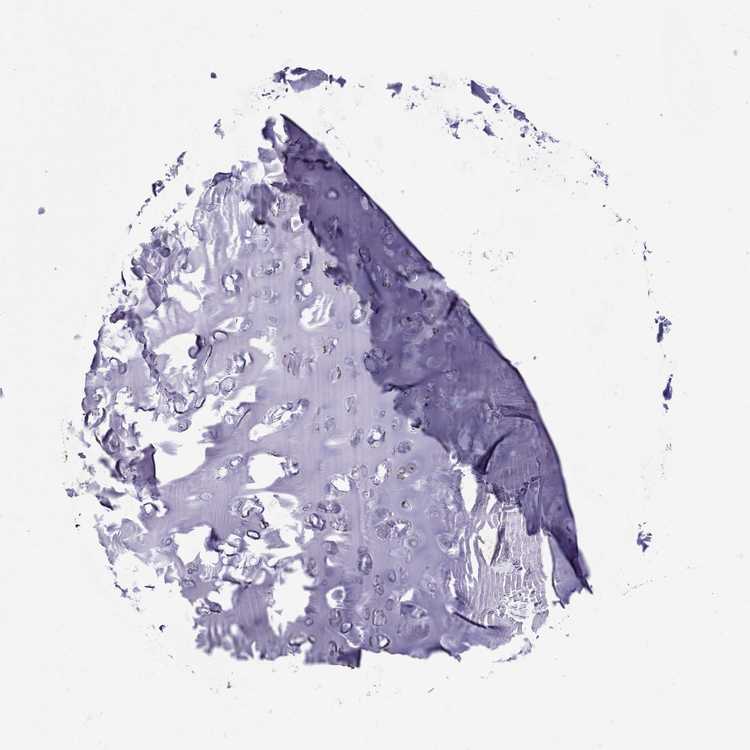

TISSUE PRIMARY DATA SOFT TISSUE Show tissue menu

SOFT TISSUE - Expression summary

SOFT TISSUE 1 - Antibody stainingi

Antibody staining in the annotated cell types in the current human tissue is reported as not detected, low, medium, or high, based on conventional immunohistochemistry profiling in selected tissues. This score is based on the combination of the staining intensity and fraction of stained cells.

Each image is clickable and will lead to virtual microscopy that enables deeper exploration of all samples and also displays staining intensity scores, fraction scores and subcellular localization as well as patient and tissue information for each sample.

Antibody HPA022035Antibody HPA063619

Chondrocytes MediumNot detected

Fibroblasts LowNot detected

Peripheral nerve Medium-

SOFT TISSUE 2 - Antibody stainingi

Peripheral nerve MediumNot detected